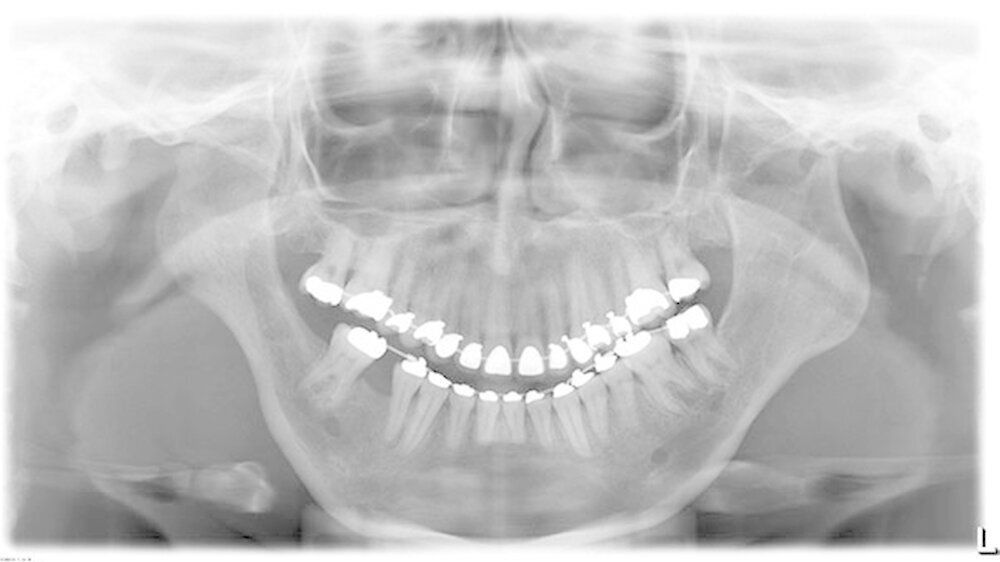

Durch diese hoch anspruchsvollen Verfahren ließ sich annähernd die ursprüngliche Position des Unterkiefers vor der Einschmelzung wiederherstellen; in der gleichen Operation wurde die Position des Oberkiefers der jetzt idealen Stellung des Unterkiefers angepasst.

Die Patientin erreicht dauerhaft eine Mundöffnung von 35 mm ohne Schmerzen, kann jede Nahrung zu sich nehmen und hat einen stabilen Zusammenbiss der Zähne - auch die erhebliche Rücklage des Unterkiefers ist dauerhaft beseitigt.